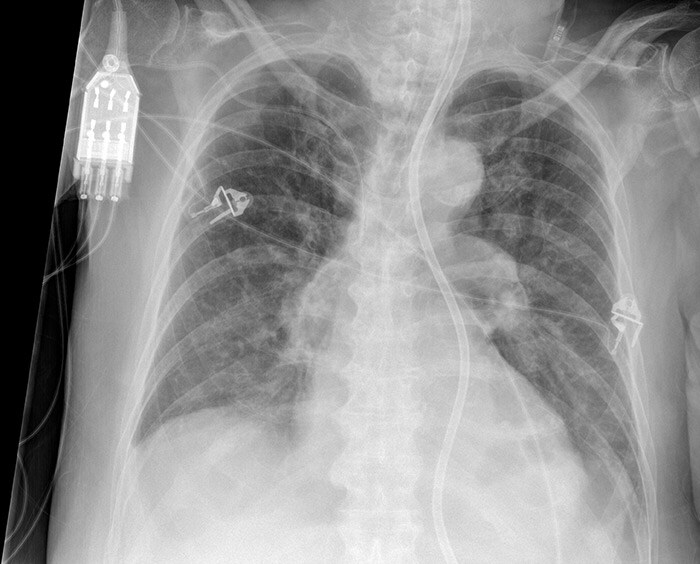

Bedside chest xray showing the cardiac resynchronization therapy Bedside Chest X Ray The bedside chest radiograph is an indispensable diagnostic tool in the management of critical patients admitted in the intensive. Bedside Chest X Ray.